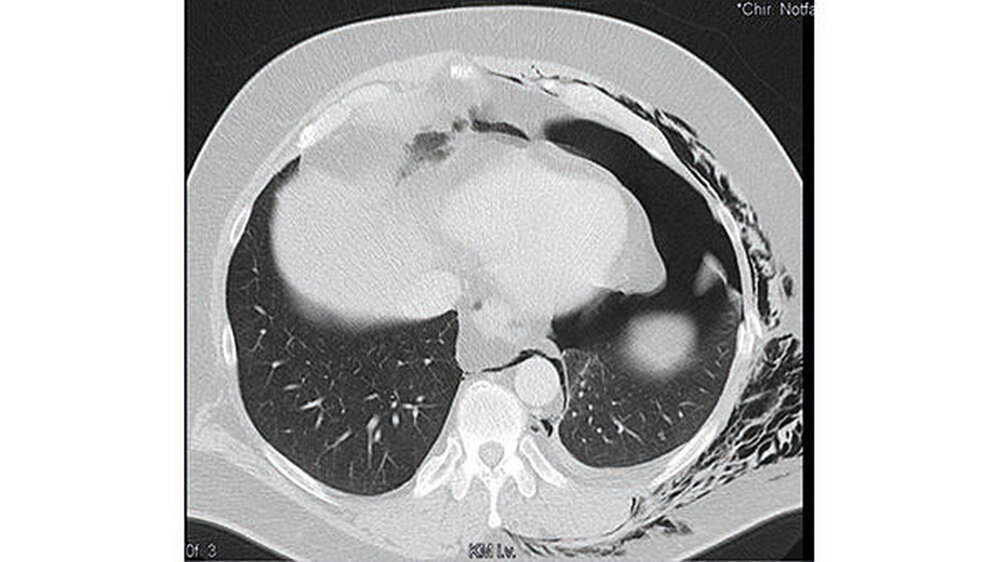

Diese zeigte nun Frakturen der siebten bis neunten Rippe links lateral, einen linksseitigen Mantelpneumothorax sowie ein ausgedehntes Weichteilemphysem mit Einstrahlen in den Hals, in den Rücken sowie in das Mediastinum (Abbildung 6).